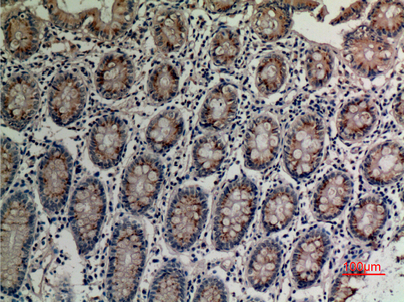

Immunohistochemical analysis of paraffin-embedded human-colon, antibody was diluted at 1:100